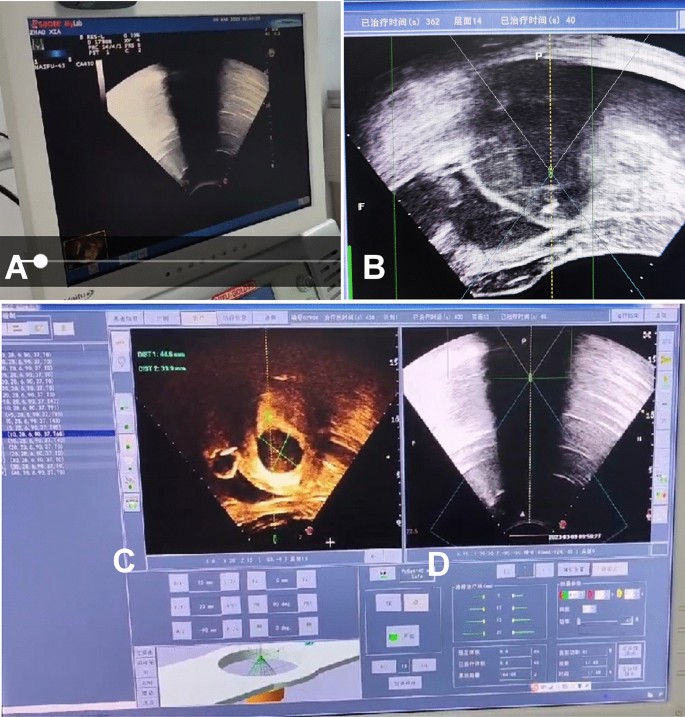

During the treatment, real-time monitor with a diagnostic ultrasound system was performed to observe the changes of lesion and surrounding normal tissues in real time so as to focus energy on the treatment area and avoid damaging surrounding tissues (Fig. 1). When there was an obvious gray increase or mass gray in the target area, coagulative necrosis in the treatment area could be confirmed, and treatment was then move to the next point until the whole area was completely treated. During treatment, if the patient had abdominal skin burning pain or lumbosacral, hip and lower limb pain, the irradiation treatment was stopped.

Real-time ultrasound monitoring of treatment of uterine ademomyosis with high-intensity focused ultrasound (HIFU). (A) Imaging of real-time ultrasound monitoring was displayed on the screen of one ultrasound scanner. (B) Real-time ultrasound monitoring showed that the total treatment time was 362 s, the treatment was on the 14th layer, and the treatment time on this layer was 40 s. (C) HIFU treatment imaging was displayed on the monitor screen of HIFU scanner. (D) The imaging of real-time ultrasound monitoring (A) was transferred to the HIFU screen (D) for real-time monitoring of the HIFU treatment effect, and if the treatment caused significant gray increase in the whole lesion area, the HIFU treatment would be stopped.